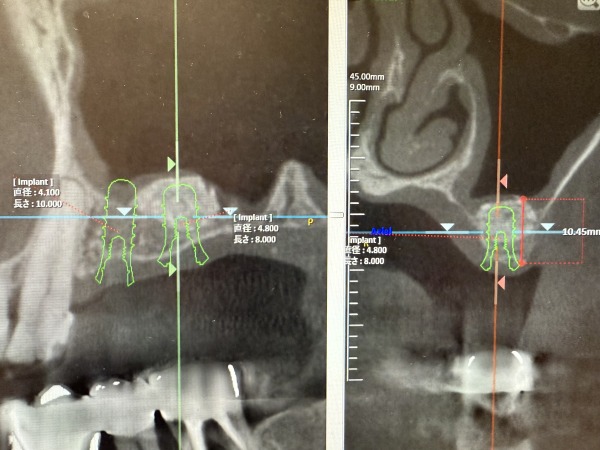

術前後のCT画像がこちらになります。3mm以下であった骨の厚みが10mm程度に増加しております。

サイナスリフトを行い6ヶ月ほど経過した時点で、CTを撮影しインプラントが問題なく入れられることを確認しました。十分な骨の中にインプラントが埋め込まれているのが分かるかと思います。